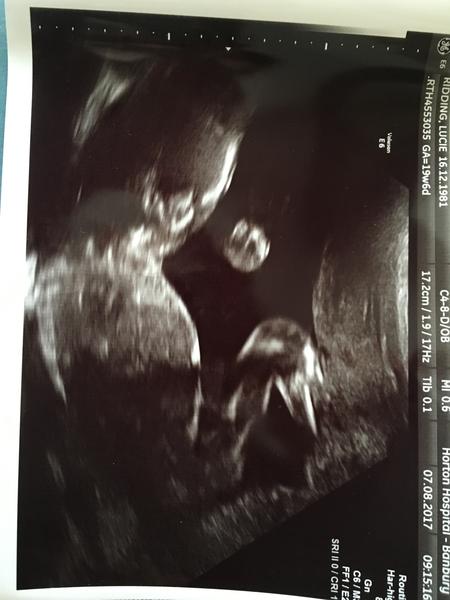

Holky jsem šťastná jako blecha krevní testy na vyvojove vady dopadly dobře a čekáme vytouženou holčičku.🙏

@vvercatkoo děkuji. Chteli jsme to vědět a z těch krevnich testů je to spolehlivé tak uvidíme na příštím ultrazvuku jestli nam to potvrdí😁